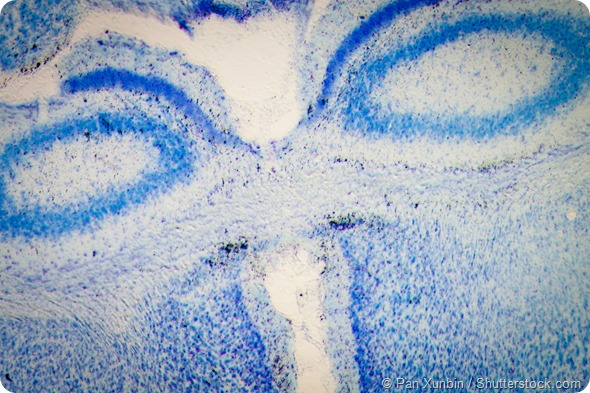

science medical microscopy micrograph, rat brain hippocampal neurons

Rat brain hippocampal neurons - microscopy micrograph.